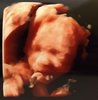

Połówkowe - wyniki

OM 21+4 tc

USG 21+1 tc

Wszystkie narządy prawidłowe

Waga: 420 g

Tętno 148

Szyjka 4,6

Płeć : dziewczynka